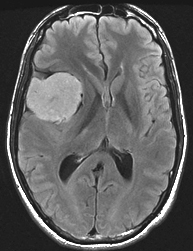

Imagerie IRM conventionnelle :

Volumineuse lésion temporale droite apparaissant sous forme d’une masse bien limitée, en hypersignal FLAIR relativement homogène. En T2, aspect hyperintense plus hétérogène, pseudo-lobulé.

Après injection de gadolinium, très importante prise de contraste un peu hétérogène ; à noter une prise de contraste méningée associée à type de « dural tail » traduisant une réaction de voisinage et l’origine méningée probable de la lésion.